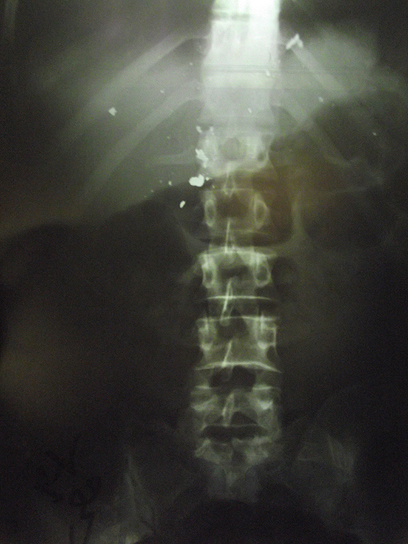

Ynet has obtained x-rays from the Rafidia Hospital in Nablus which prove that one of the victims was hurt by live fire. Doctors retrieved bullet parts from his body and the x-rays show that the bullet was lodged near the victim's spine.

Hospital director Dr. Osama Malhis, said that the bullet had entered the victim's body through his stomach and hit his liver. He said that it was a hollow-point type bullet.

X-ray of victim's spine (Photo: Zakaria Sade, Rabbis for Human Rights)